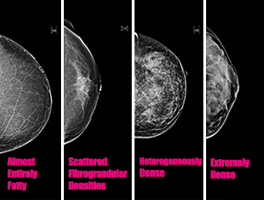

Make Your Mammogram a Must

Breast cancer is a bully who’s willing to pick a fight with just about anyone. Almost everyone knows someone affected by the disease, making every day the perfect day to talk about early detection, the differences in screening technology and what else you can do to reduce your risk. 2D Versus 3D Mammography When you […]